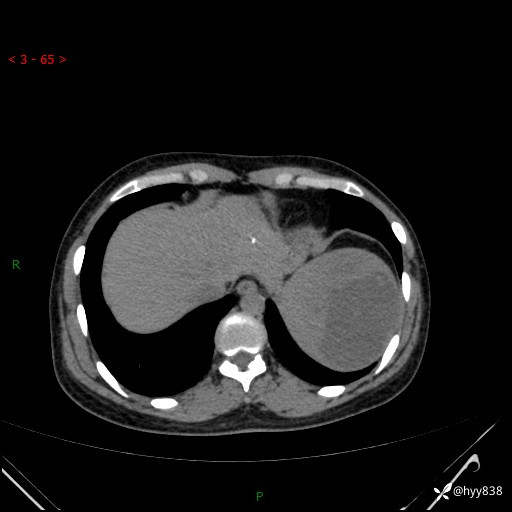

患者性别:男

患者年龄:44岁

主诉:外院超声发现脾脏占位,来我院进一步诊治。

辅助检查:CT

临床诊断:脾脏占位

脾脏CT平扫+增强(动脉期+静脉期)